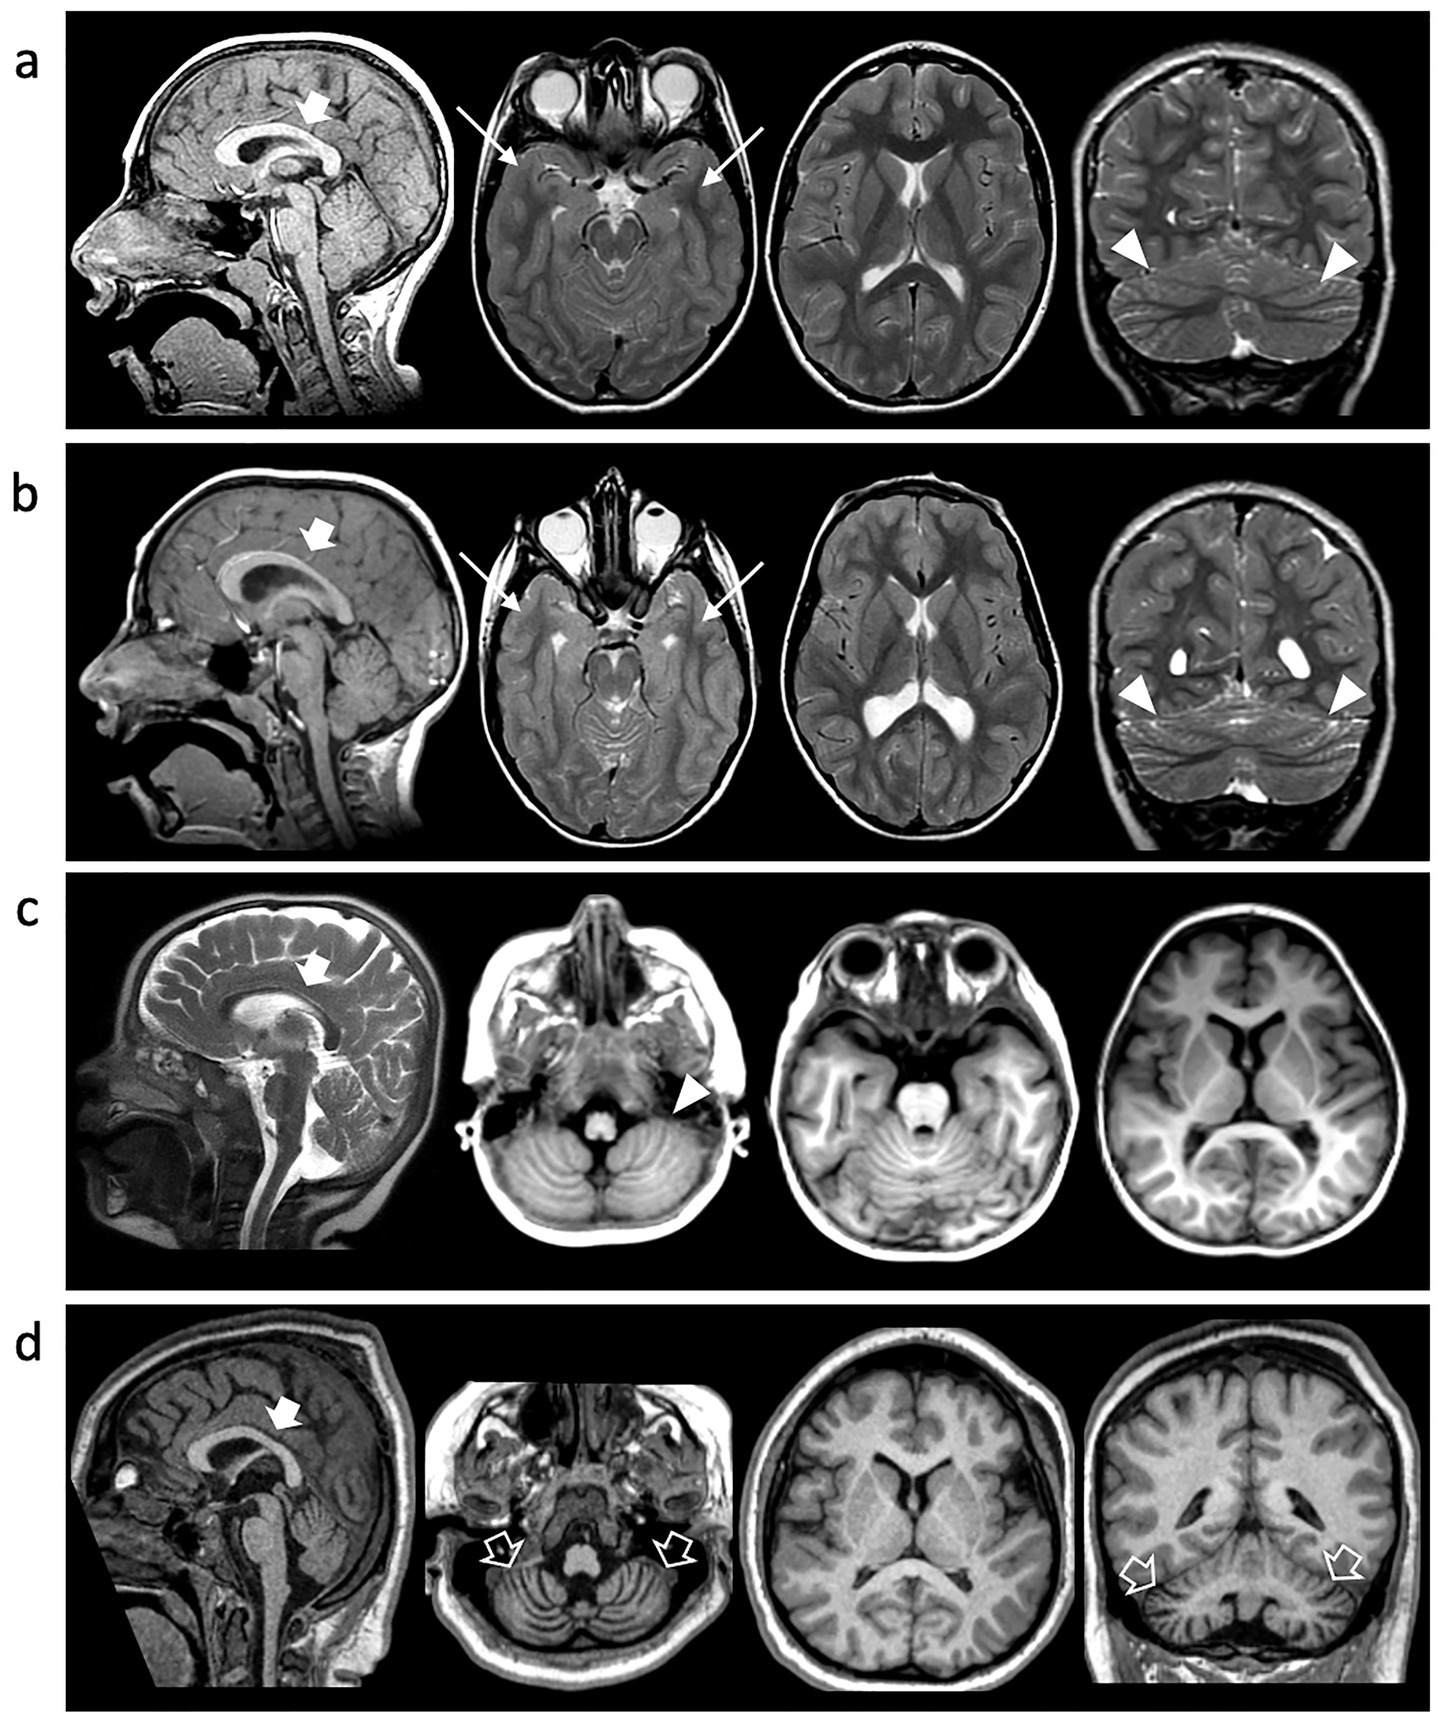

Figure 3. Neuroimaging findings. Brain MRI of Individual 1 at 10y (A), Individual 2 at 7 y (B) and Individual 4 at 2 y (C) and 10y (D). Sagittal T1 or T2-weighted images (first column), axial images (second and third columns), and coronal images (last column). Microcephaly with disproportionally large corpus callosum (thick arrows), simplified gyral pattern and cerebellar foliar anomalies are noted in all cases (arrowheads). There is bilateral temporo-basal dysgyria in Individual 1 and Individual 2 (arrows). Progressive cerebellar atrophy is detected in Individual 3 over the course of 8 years (empty arrows).

A 15-year-old boy, born at term following an uneventful pregnancy, exhibited postnatal microcephaly and turricephaly during early infancy. Early neurodevelopment was marked by global delay, reduced muscle tone, impaired primitive reflexes, and poor verbal output limited to non-purposeful syllables. By age 2 years, exaggerated deep tendon reflexes and ataxic gait emerged. Formal neuropsychiatric evaluation confirmed features consistent with ASD, including impaired communication and relational functioning. On his examination at our department at the age of 4 years, microcephaly was documented at -2SD and behavioral stereotypies, sensory-seeking behaviors, and tiptoe walking were also documented. ADOS-2 confirmed ASD diagnosis, and Risperidone was introduced with partial behavioral benefit. Follow-up at the age of 10 years revealed improved receptive language but persistent absence of expressive speech. Brain MRI at this age showed microcephaly with disproportionally large corpus callosum, simplified gyral pattern, bilateral temporo-basal dysgyria, and cerebellar foliar anomalies (Figure 3). Array-CGH identified a paternally inherited 16p13.11 duplication of uncertain clinical significance. WES revealed a novel TUBB2A variant (c.1172G > A; p.Arg391His). The variant was absent in the parents.

At age 7, he developed sleep-related seizures characterized by myoclonus and tonic posturing. Seizure control was achieved with Clobazam after failure of Valproic Acid. At 9 years, EEG showed mild anterior-predominant abnormalities. Brain MRI revealed microcephaly with disproportionally large corpus callosum, simplified gyral pattern, temporo-basal dysgyria, thinning of the periventricular white matter with symmetric ventriculomegaly, and cerebellar foliar anomalies (Figure 3). Genetic testing was negative by array-CGH. WES confirmed the same heterozygous TUBB2A p.Arg391His variant identified in his brother. The variant was absent in the parents.

Individual 4 is a 14-year-old female born to unrelated parents. The patient has microcephaly and global developmental delay with progressive loss of motor milestones; she initially was able to sit without support and stand with support, but by the age of 4 was no longer able to sit unsupported. The patient is currently non-verbal and with limited communication. She developed refractory epilepsy with multiple seizure types and subsequently manifested hyperkinetic movement disorders including choreoathetosis. Respiratory compromise emerged at the age of 10 years, necessitating tracheostomy and G-tube feeding due to neuromuscular dysphagia. She also developed progressive (neuromuscular) scoliosis and is wheelchair-dependent requiring adaptive equipment. Neuroimaging at age 2 showed microcephaly with disproportionally large corpus callosum, simplified gyral pattern, and cerebellar foliar anomalies, and by age 10, marked cerebellar atrophy and periatrial white matter signal changes were evident. WES identified the same de novo TUBB2A variant (c.1172G > A; p.Arg391His).

Interestingly, all subjects presented with microcephaly and a simplified gyral pattern at the time of presentation. Temporo-basal dysgyria was observed in two individuals, and cerebellar foliar anomalies were noted in three cases. The corpus callosum appeared disproportionately large relative to the degree of microcephaly. Notably, none of the patients exhibited the hallmark features of tubulinopathy, such as asymmetric ventriculomegaly and basal ganglia dysmorphisms. Moreover, dysgyria was noted only in two cases and was limited to the temporo-basal regions. One individual demonstrated a progressive phenotype, developing cerebellar atrophy over an eight-year period. Cerebellar atrophy is, in fact, a recognized feature in certain tubulinopathies, particularly those linked to mutations in the TUBB4A gene, such as Hypomyelination with Atrophy of the Basal Ganglia and Cerebellum.